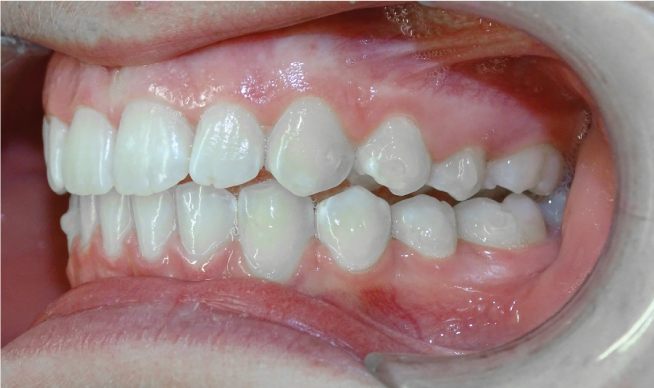

La classe II est fréquente en orthodontie et son traitement dépend non seulement du diagnostic mais aussi de l'évolution des appareillages. Nous traitons toutes les classes II avec Invisalign depuis 2008 et sans bagues quelle que soit la déformation ou la cause.

La classe II, c’est quand la mâchoire du bas est en arrière de la mâchoire du haut, donnant l’effet de “dents en avant” pour la mâchoire du haut. Si c’est normal à la naissance, Ceci paraitrait normal à la naissance et tend à se corriger avec l’allaitement maternel et la recherche de contacts entre les incisives du haut et du bas. Au plus on intervient tôt, au plus la mâchoire du bas va rattraper la mâchoire du haut ; au plus on attend, au plus on reculera le haut sur le bas avec des conséquences sur l’esthétique du profil et la capacité ventilatoire nasale.

Dans le cas d’une Classe II :

• La lèvre du bas s’interpose entre les 2 mâchoires

• Le sourire est étroit, tendance à l’écrasement du bas du visage